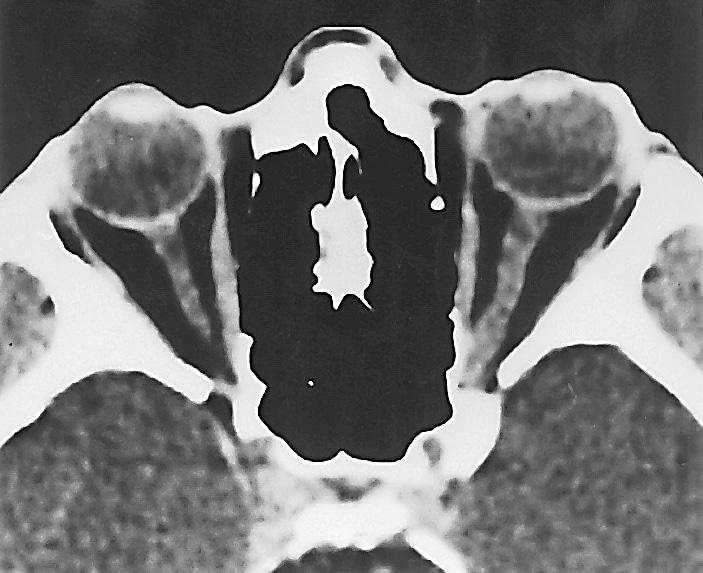

venstre øye høyre øye chiasma opticum n. opticus tractus opticus corpus geniculatum laterale area striata radiatio optica Figur 2.18 Synsbanen. Figur 2.19 Computertomografi (Ct) av øyehulene med synsnervene.

Figur 2.20A magnetisk resonanstomografi (mR) av øyehulene og hjernen. Figur 2.20B mR viser synsnervene, chiasma opticum og overgang til tractus opticus.